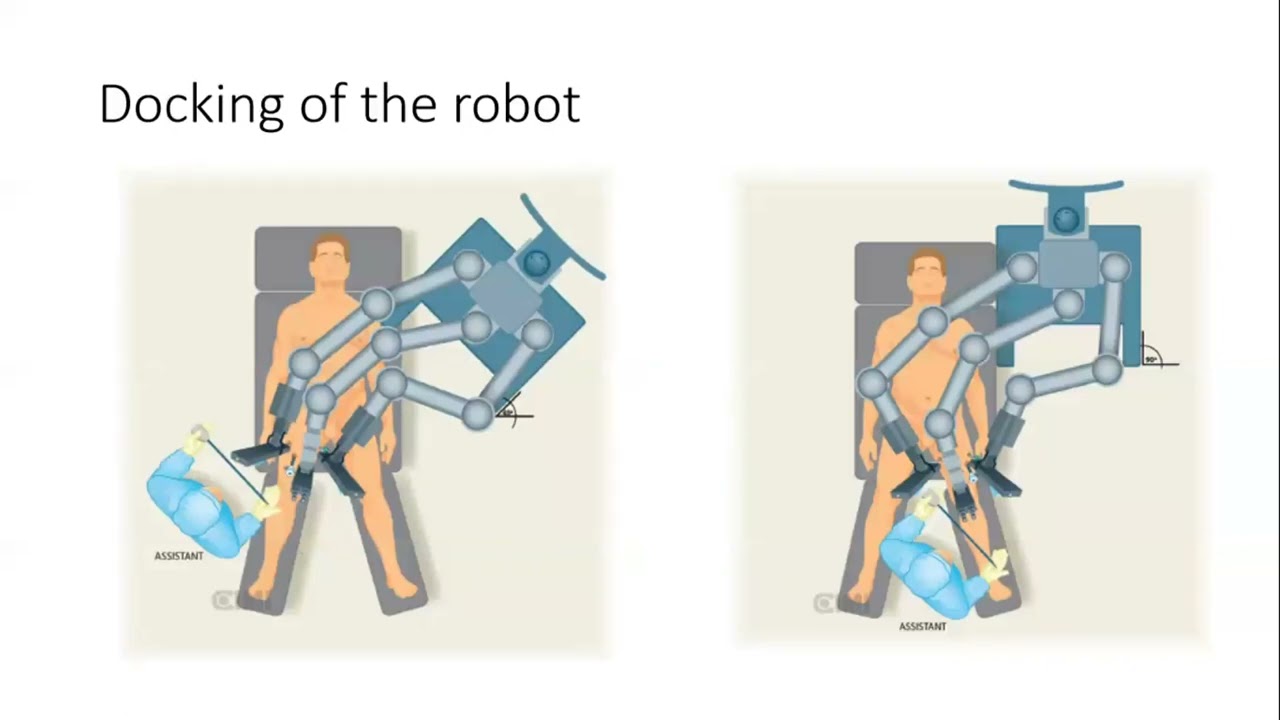

Robot-assisted radioguided surgery using a DROP-IN gamma probe